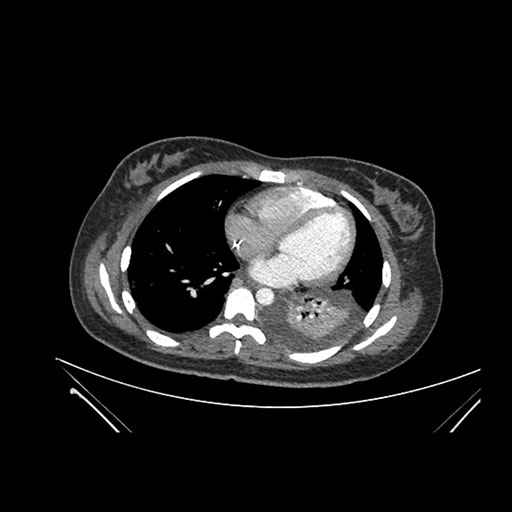

Axial Arterial